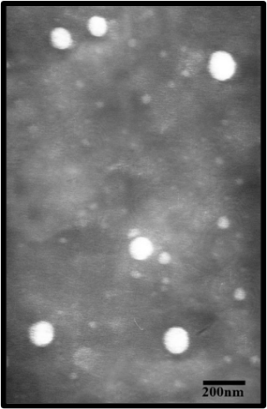

Transmission electron microscopy (TEM)

TEM analysis was used to examine the red fruit oil nanoemulsion morphology. The nanoemulsion was dissolved in aqua dest (1/100), dropped on a holey film grid, and analyzed using TEM after drying [17].

The red fruit oil nanoemulsion was cloudy red, smelled strongly of red fruit oil, and did not undergo phase separation. The nanoemulsion viscosity study at 4 rpm yielded a value of 531.5 cP. The nanoemulsion of red fruit oil had pseudoplastic flow properties (fig. 2). Measurements found that the pH of the nanoemulsion was 4.5-6.5 and thus suitable for the pH of the skin. The obtained nanoemulsion particle size was 103.07±1.31, with a PDI of 0.229±0.02 (table 5). The particle formed was small for penetration of the wall of the film surfactant by the co-surfactant, which later reduced the fluidity and viscosity of nanoemulsion [27]. Using TEM (JEOL 1010, USA), the morphology of the red fruit oil nanoemulsion preparation can be seen microscopically. The result showed that the red fruit oil nanoemulsion preparation has a spherical shape of 200 nm (fig. 3).

Fig. 3: Morphology of red fruit oil nanoemulsion